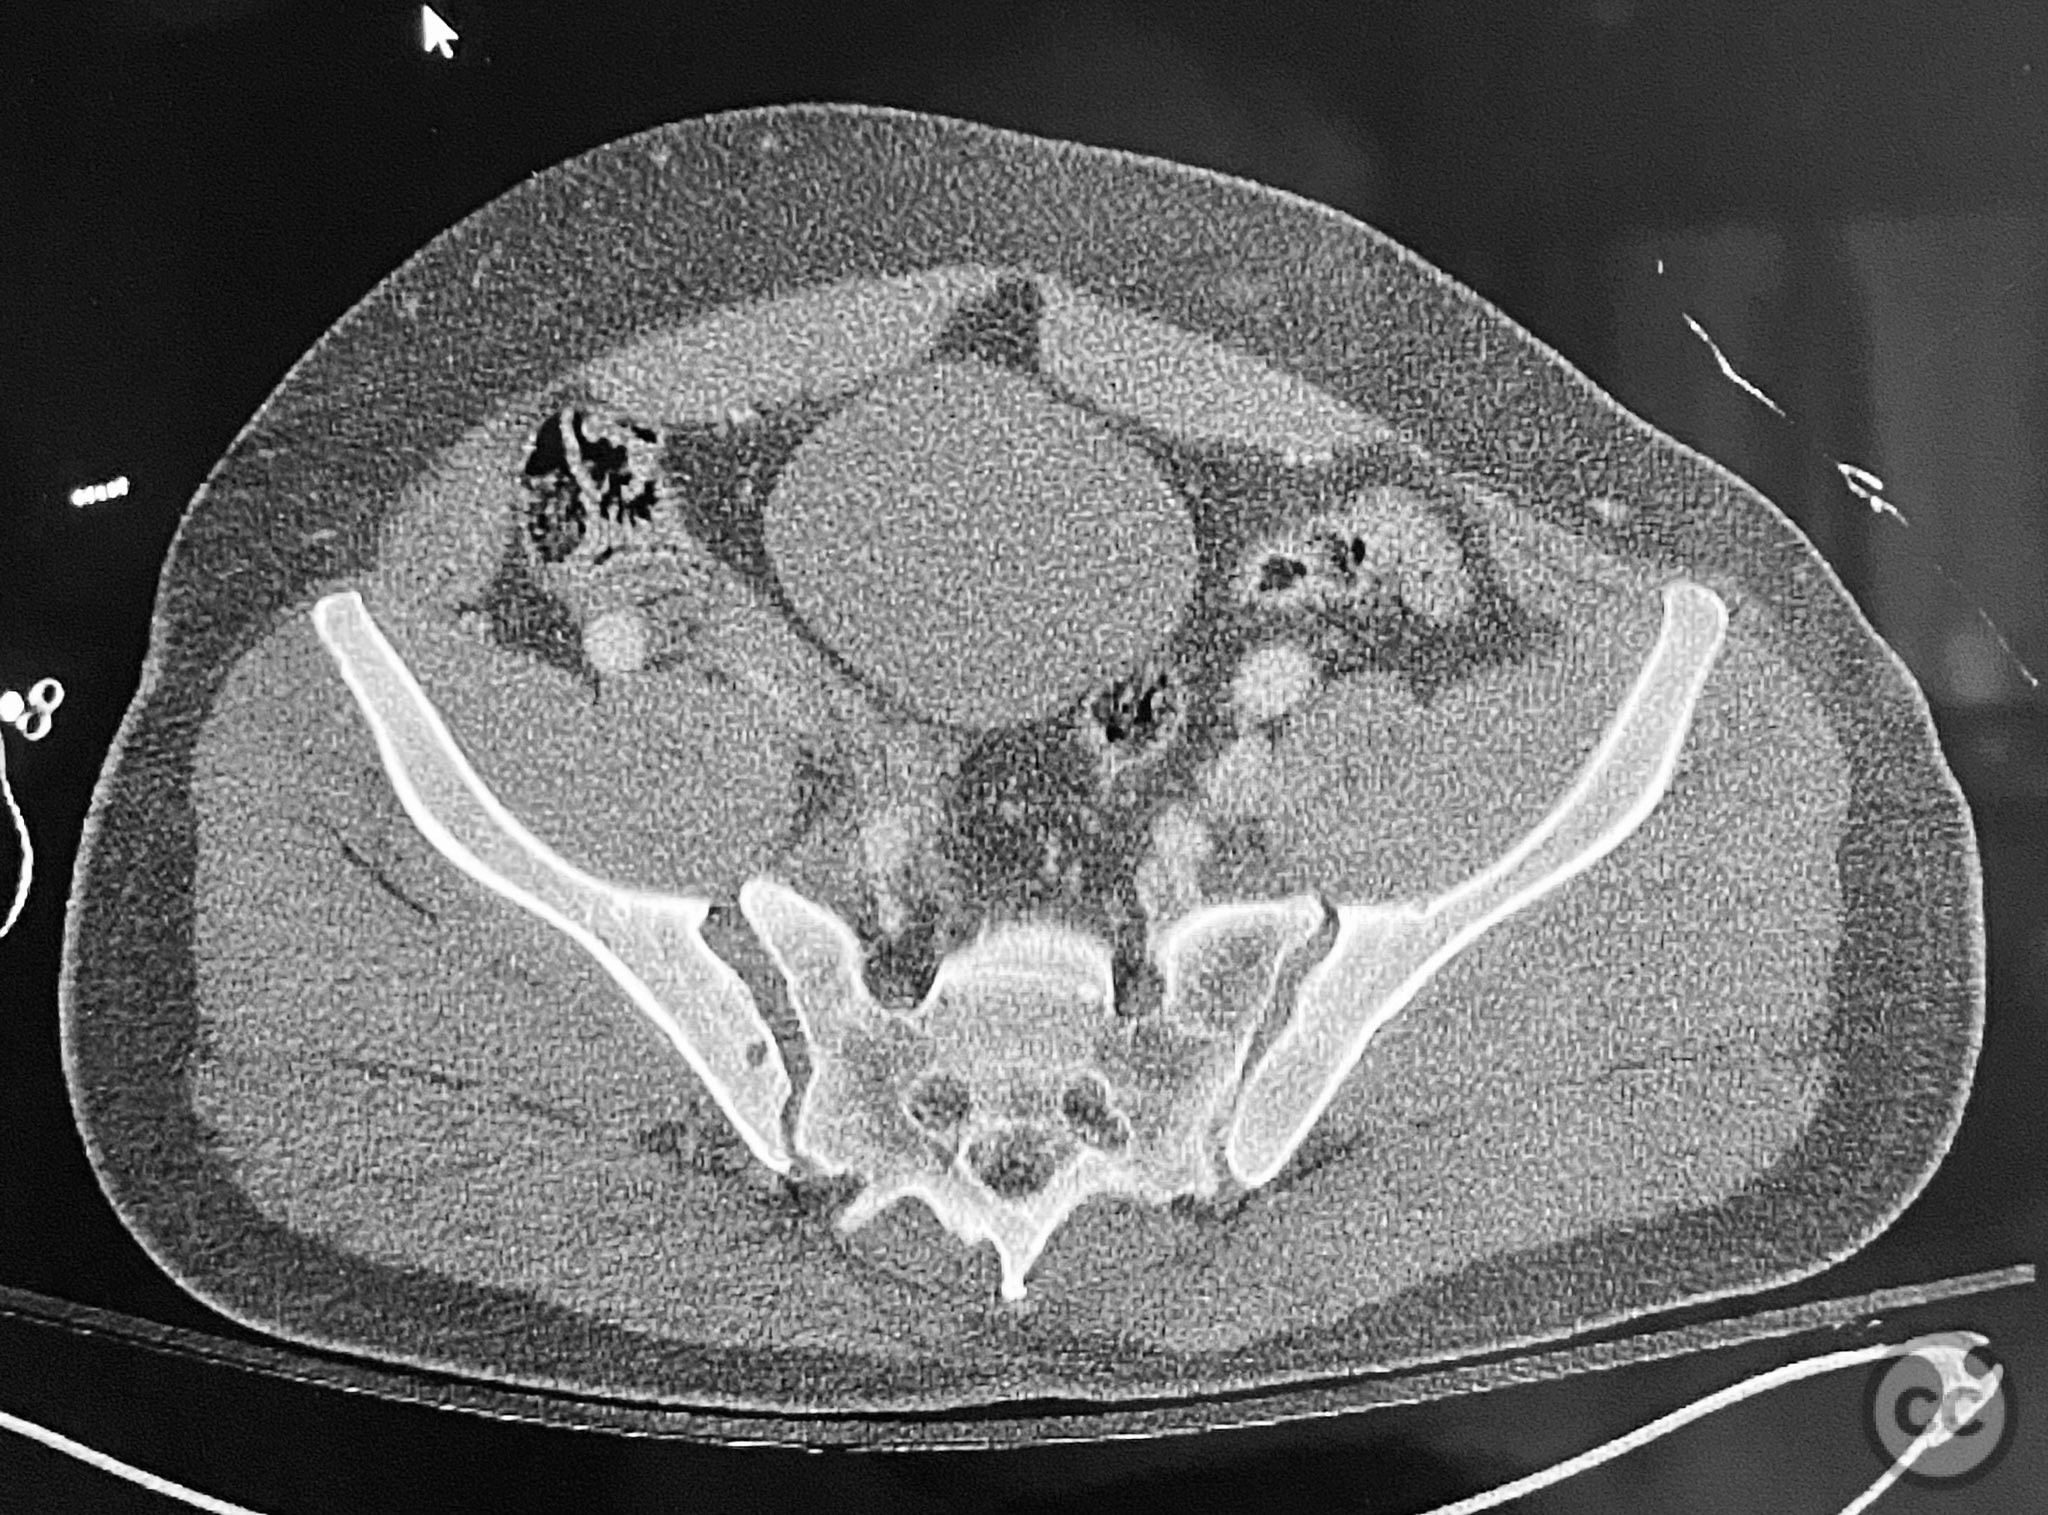

Clinical and radiological findings:  Adult male with a closed, comminuted left femoral shaft fracture and complex pelvic ring injury. Initial imaging demonstrated bilateral sacroiliac (SI) joint disruptions and a left-sided transtectal transverse acetabular fracture (Letournel-Judet: transverse type), with the fracture line exiting through the posterior wall region but without a discrete posterior wall fragment. The femoral head was displaced caudally, following the unstable distal acetabular segment, resulting in loss of congruency with the intact acetabular dome. There was also a symphyseal disruption. No associated abdominal, visceral, thoracic, cranial, or other injuries were present. Application of a circumferential pelvic binder resulted in visible changes in pelvic alignment on imaging. AO/OTA Classification: - Pelvic ring: 61-C1.3 (bilateral SI joint disruption, complete instability) - Acetabulum: 62-B1 (transverse fracture) - Femur: 32-C3 (comminuted diaphyseal fracture)

Planning remarks:  The preoperative plan involved staged management: initial resuscitation and provisional stabilization with a circumferential pelvic binder, followed by operative reduction and fixation of the pelvic ring using an anterior two-pin external fixator for SI joint compression and reduction, percutaneous iliosacral (IS) and transsacral (TS) screw fixation, and subsequent intramedullary nailing of the femur. Definitive acetabular fixation was planned via a posterior Kocher-Langenbeck approach in the prone position.